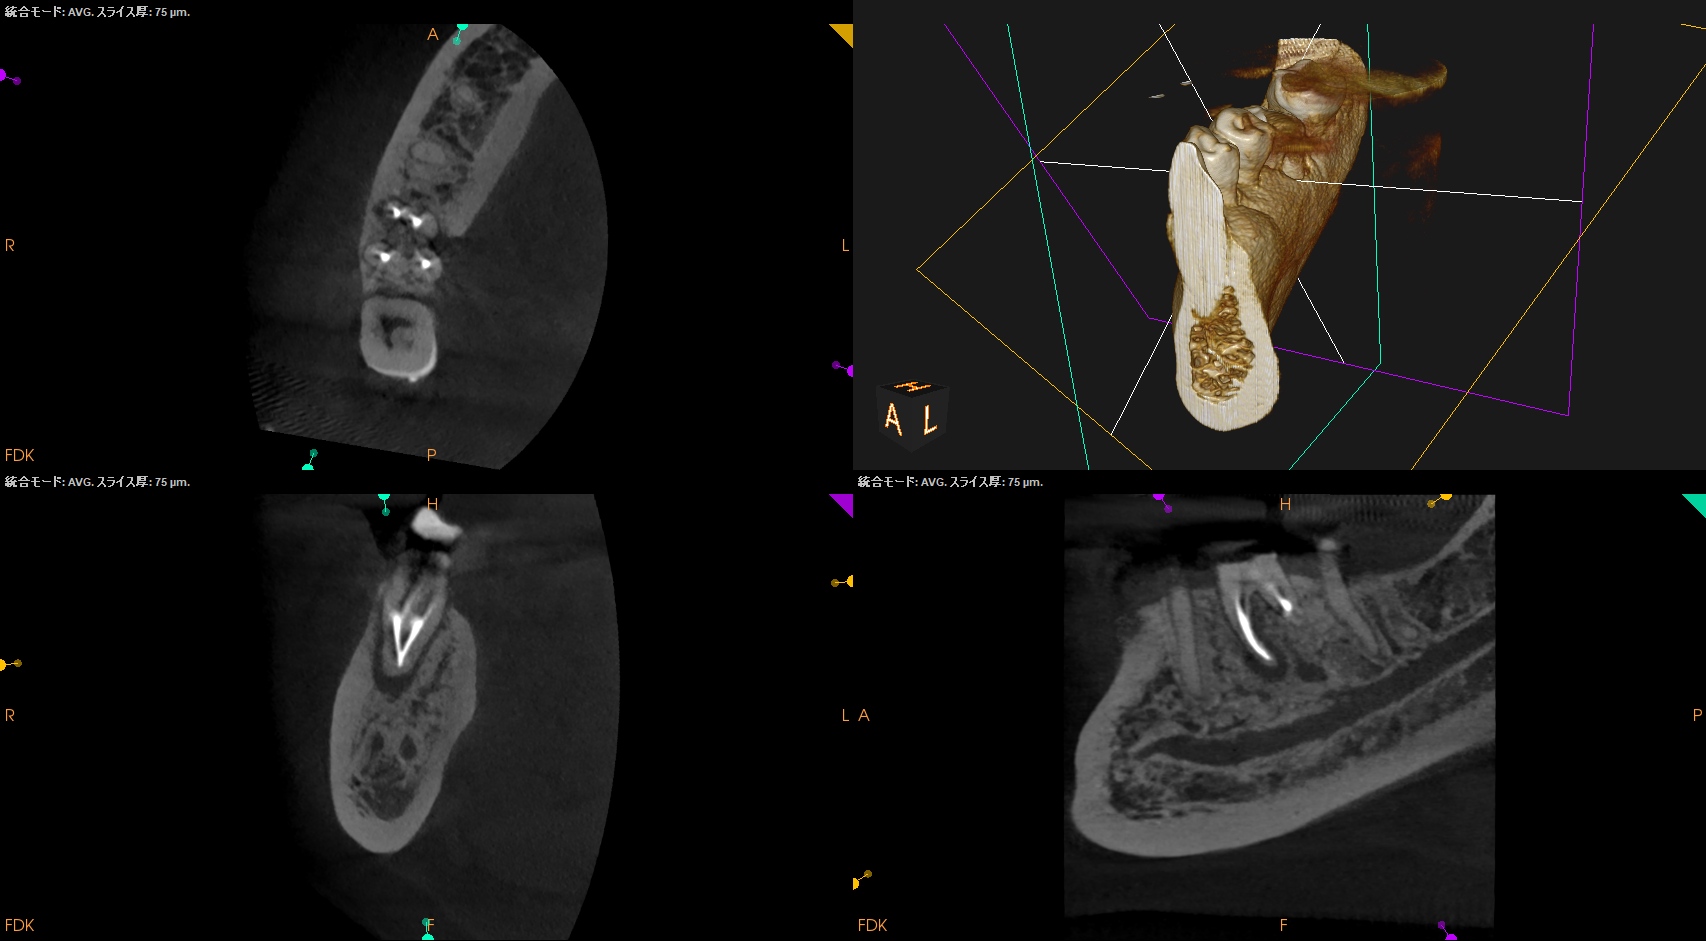

そこそこ湾曲度合いが強いRadix Entomolarisを有する#30だ。

が、D以外の根管はほぼ適切な根管治療がなされていない。

Radixにおいては未着手だ。

支台築造後にPA, CBCTを撮影した。

MB

ML

D

Radix

問題はないだろう。